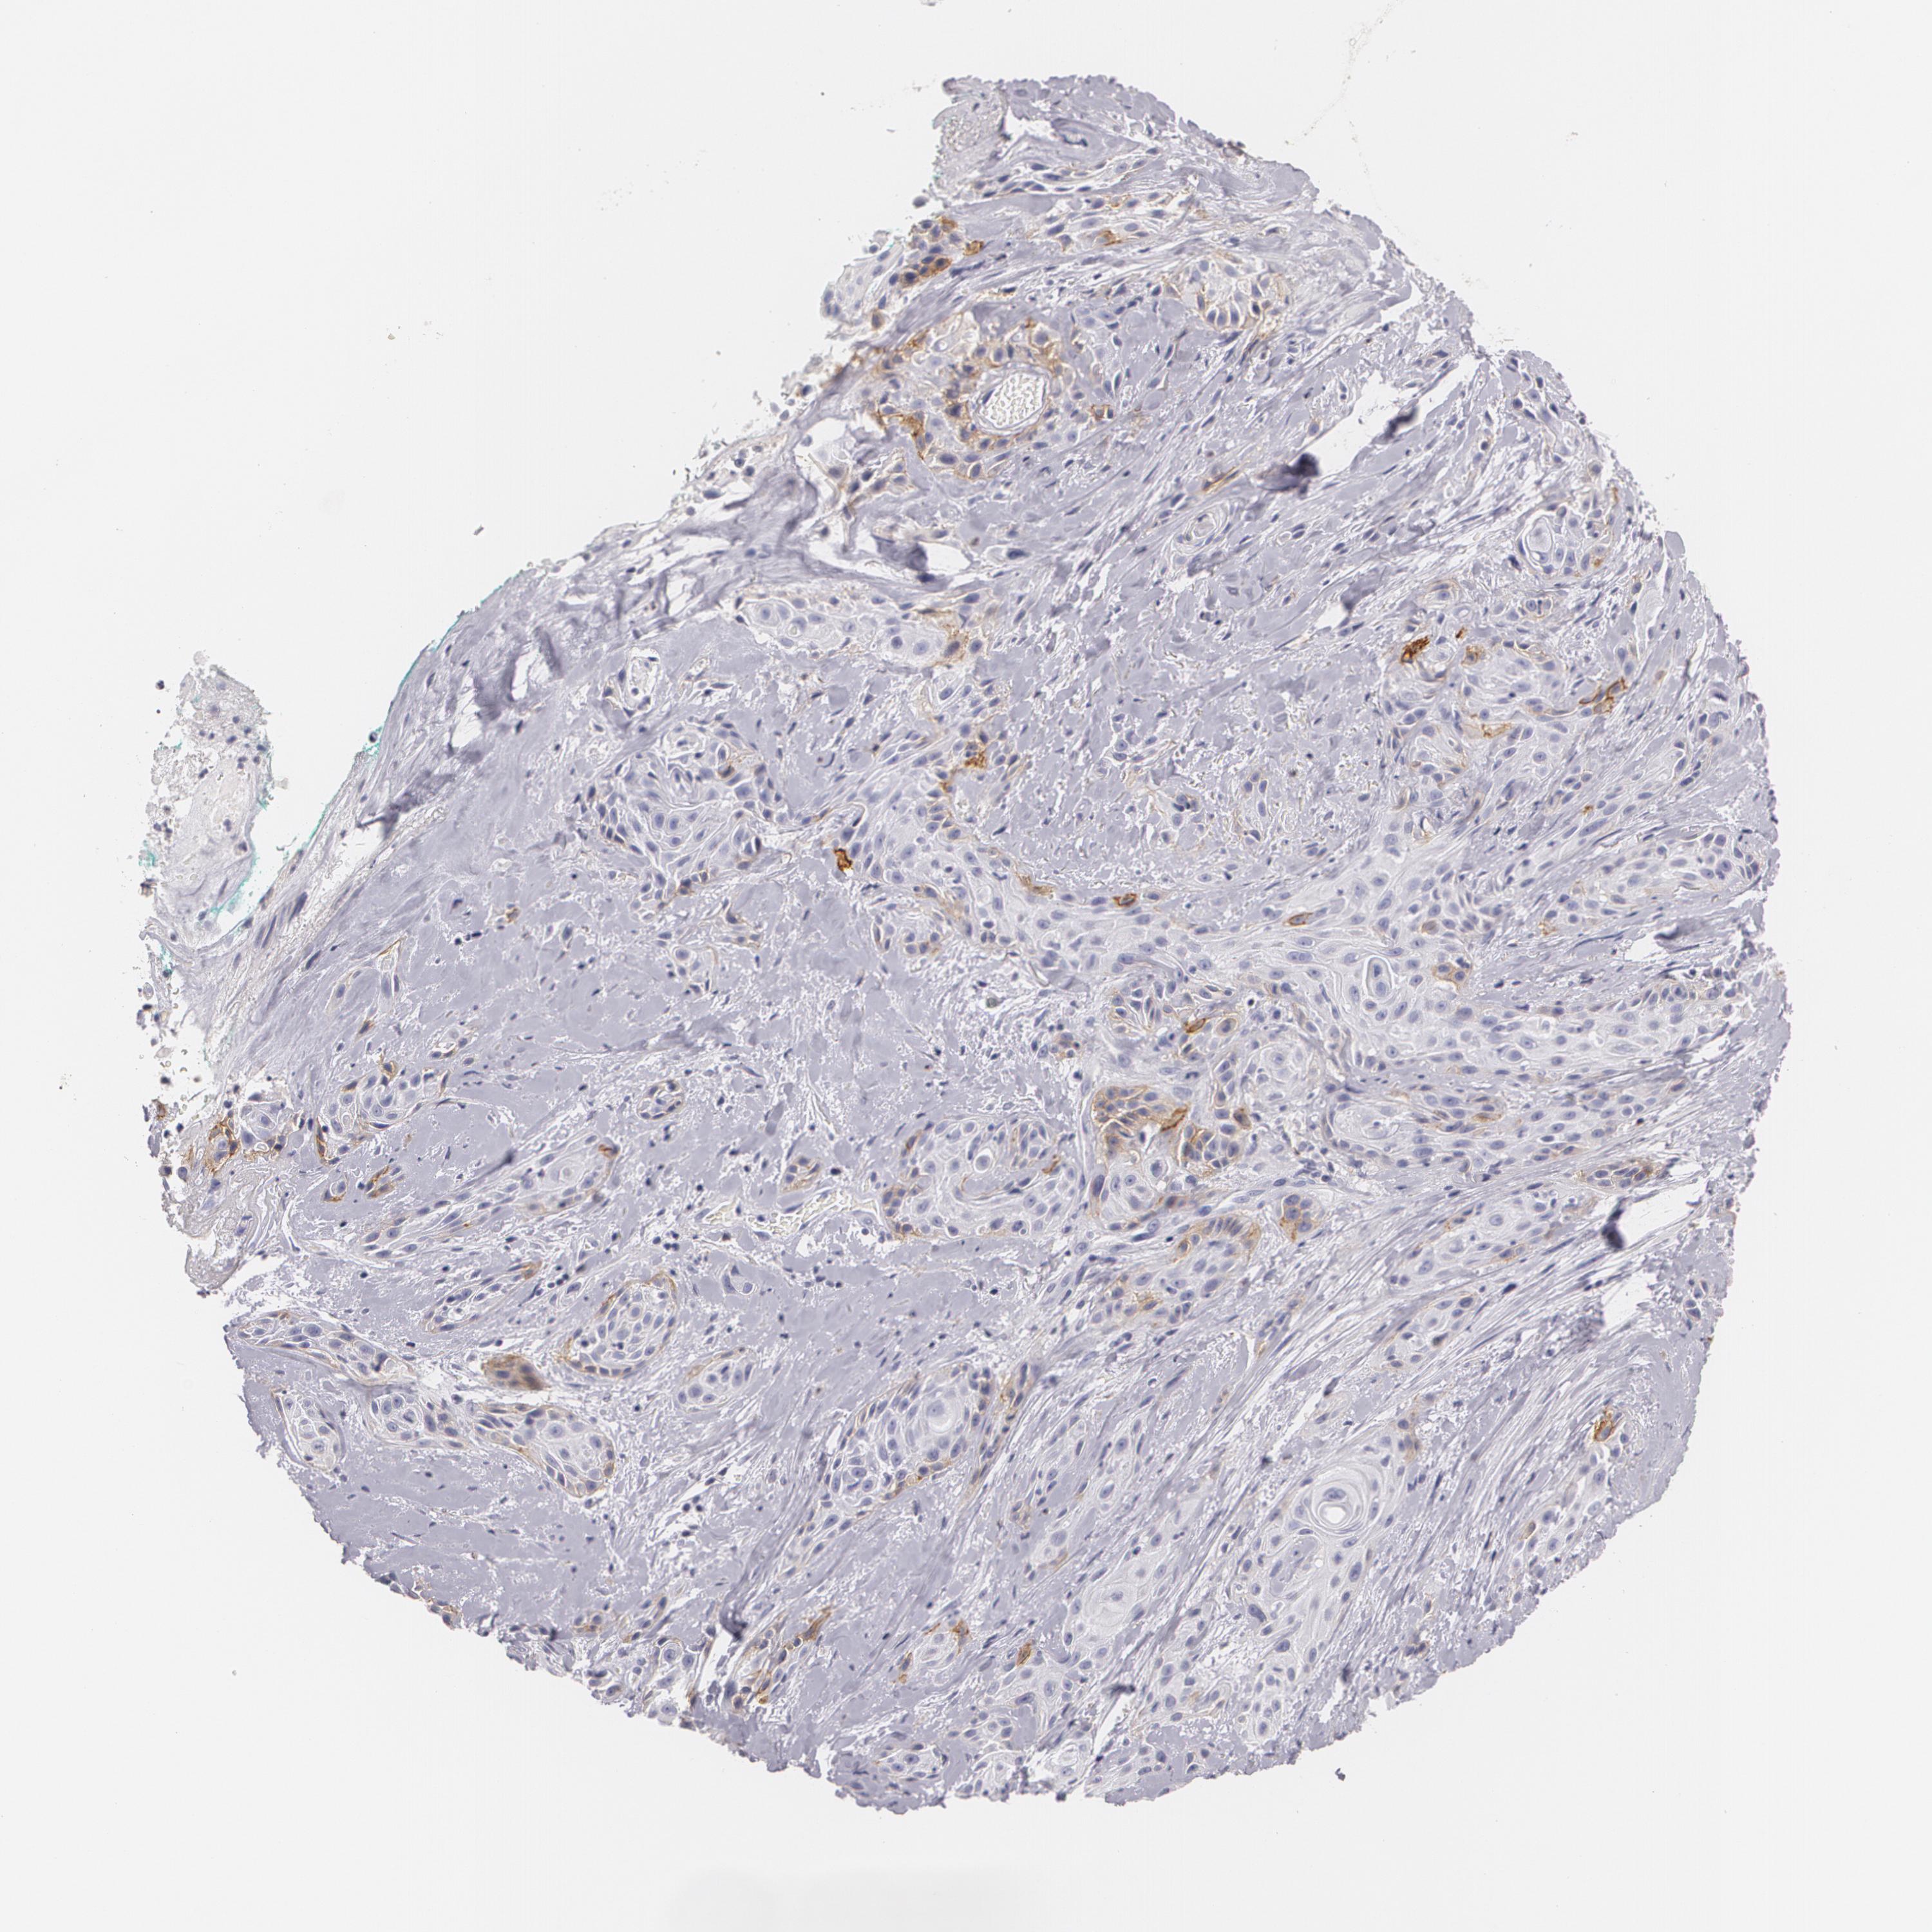

SKIN CANCER - Protein expressioni

A mouse-over function shows sample information and annotation data. Click on an image to view it in a full screen mode. Samples can be filtered based on level of antibody staining by selecting one or several of the following categories: high, medium, low and not detected. The assay and annotation is described here.

Antibody stainingi

Antibody staining in the annotated cell types in the current human tissue is reported as not detected, low, medium, or high, based on conventional immunohistochemistry profiling in selected tissues. This score is based on the combination of the staining intensity and fraction of stained cells.

Each image is clickable and will lead to virtual microscopy that enables deeper exploration of all samples and also displays staining intensity scores, fraction scores and subcellular localization as well as patient and tissue information for each sample.

Antibody HPA004765

Antibody CAB000143

Antibody CAB001995

Staining

High

Medium

Low

Not detected

Intensity

Strong

Moderate

Weak

Negative

Quantity

>75%

75%-25%

<25%

None

Location

Nuclear

Cytoplasmic/membranous

Cytoplasmic/membranous,nuclear

Squamous cell carcinoma, NOS

Basal cell carcinoma